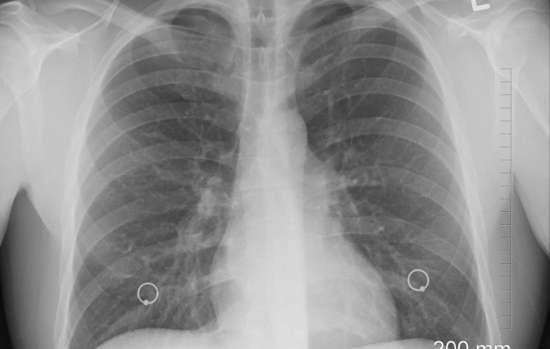

Так, у многих инфицированных с тяжелой формой заболевания наблюдается аномальная свертываемость крови. Ученые проанализировали показатели тяжелобольных ковид-пациентов и пришли к заключению, что к летальным исходам приводит образование микротромбов в легких.

С точки зрения одного из авторов научной работы, профессора Джеймса О’Доннелла, такие осложнения не возникают при других разновидностях легочной инфекции. По его мнению, это может объяснять и падение уровня кислорода в крови у пациентов с коронавирусной инфекцией нового типа.